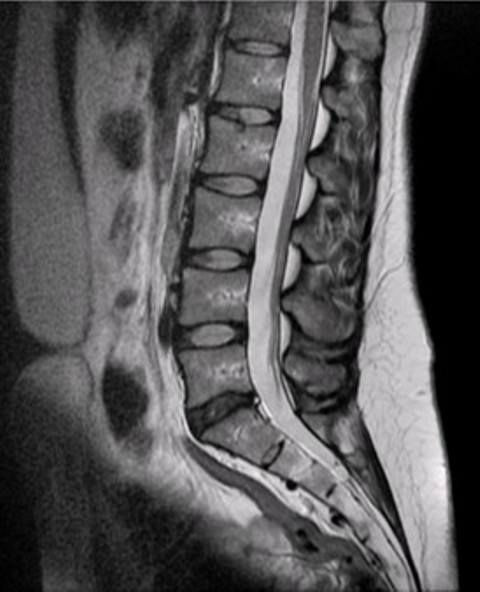

Рентгеновские снимки крестцово-копчикового отдела позвоночника